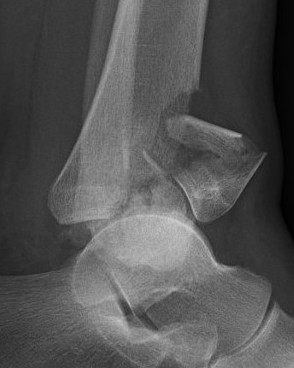

Etiology

Rapid axial load of talus into tibia

Very high energy

OTA Classfication

43-A Extra Articular

43-B Partial Articular

43-C Complete Articular